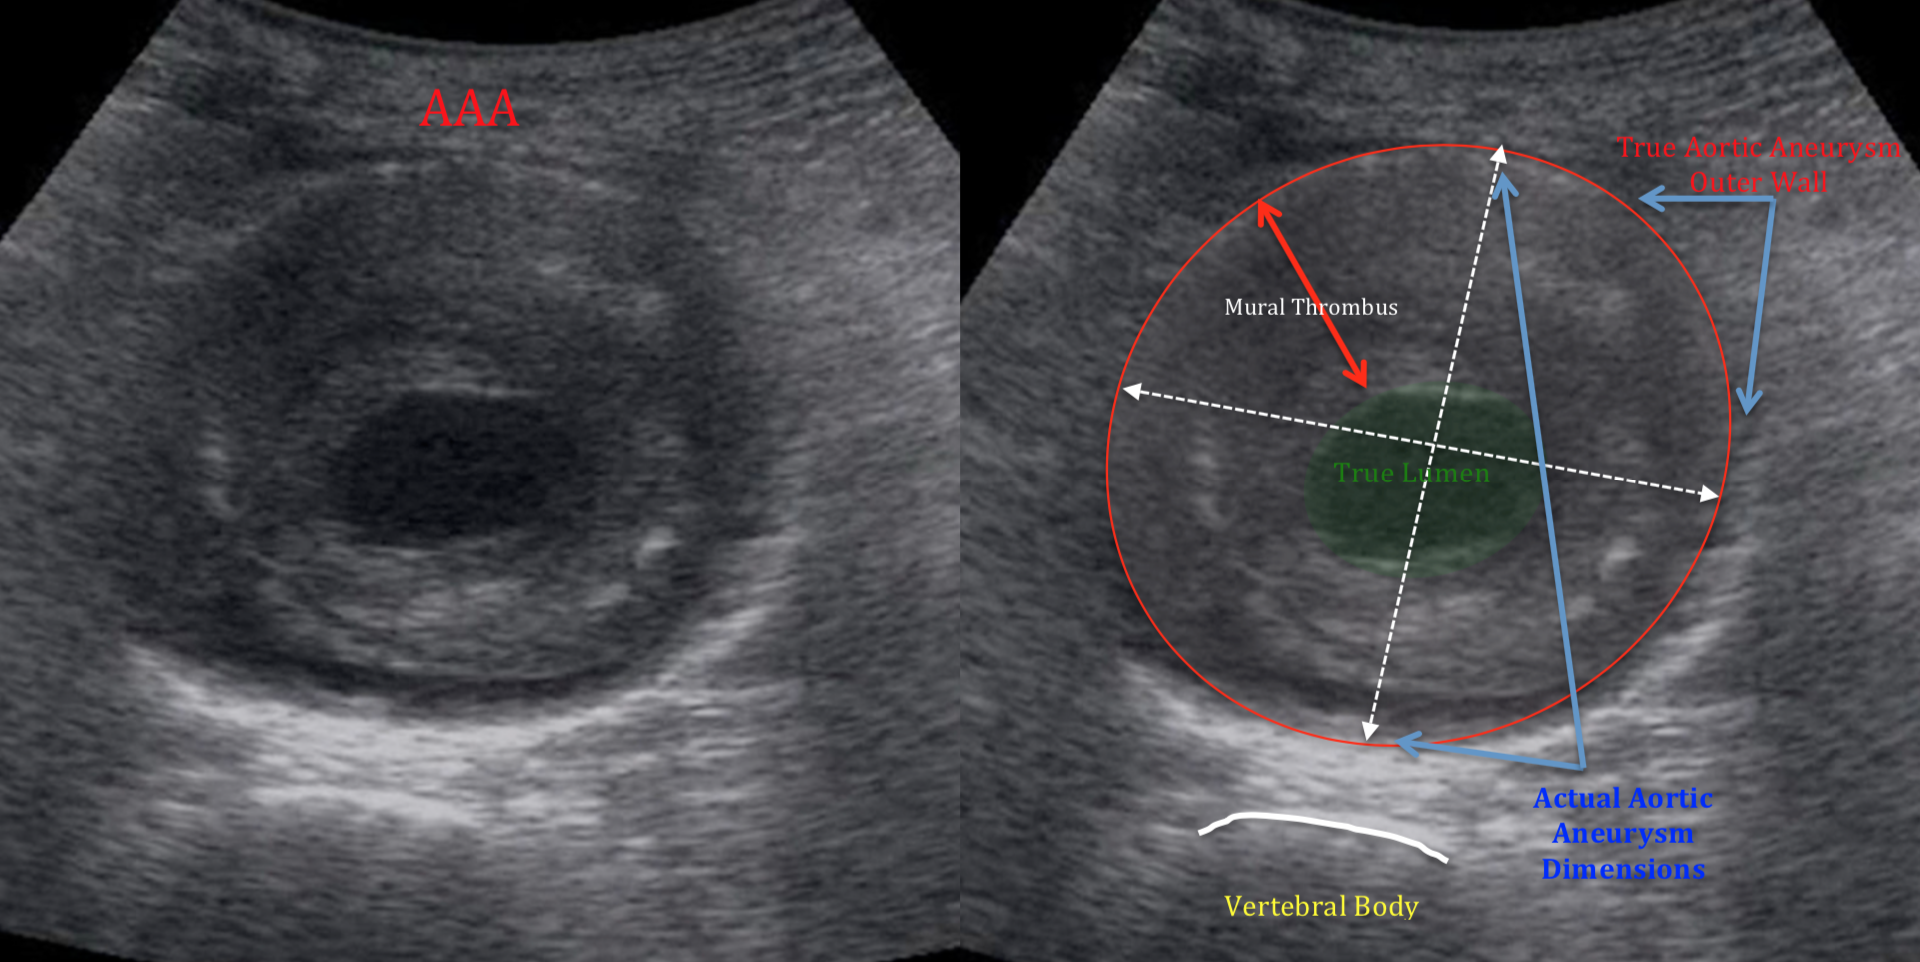

복부 대동맥류(AAA)

- 직경 3 cm 이상, 또는 정상 대비 50% 이상 확장된 상태를 말합니다.

- 5.5 cm 이상이면 파열 위험이 급격히 증가하므로 수술·스텐트 삽입을 검토합니다.

결과 해석 핵심 포인트

- 직경 < 3 cm: 정상 범주, 5년 간격 추적 권장.

- 3–4.4 cm: 소형 대동맥류, 12 개월마다 추적.

- 4.5–5.4 cm: 중간 크기, 6 개월마다 추적 + CT 추가.

- ≥ 5.5 cm: 수술·EVAR(혈관 내 스텐트) 적극 고려.